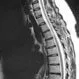

Herniated DiscA herniated disc may be caused by injury or degeneration from age. Symptoms depend on the location of the herniation and whether nerve tissue is being irritated. An MRI or CT scan is performed to diagnose a herniated disc.

SciaticaSciatica, caused by irritation of the sciatic nerve, typically radiates from the low back to behind the thigh to below the knee. Disc herniation is usually the cause of sciatica. Medication to alleviate pain, physical therapy, and bed rest are treatments for sciatica.

Picture of Slipped DiscRupturing of the tissue that separates the vertebral bones of the spinal column. See a picture of Slipped Disc and learn more about the health topic.